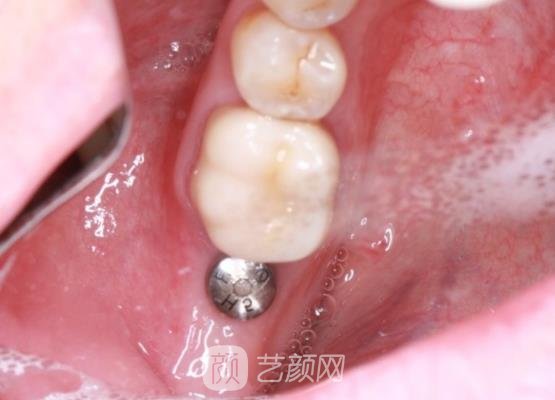

接下来手术就开始了,可能是因为医生医美技术比较厉害的原因,所以手术过程中我也没有感觉到剧烈的疼痛感,手术也没有想象中的那么可怕,两个小时以后手术就结束了。

刚结束手术的时候,我的牙龈伤口的地方有一些肿,可能是因为麻药的后劲还没有过,所以现在我也没有感觉到什么疼痛感,医生随后检查了一下我术后的口腔情况,然后按照我口腔肿胀的程度给我开了一些消炎药,提醒我定时服用。